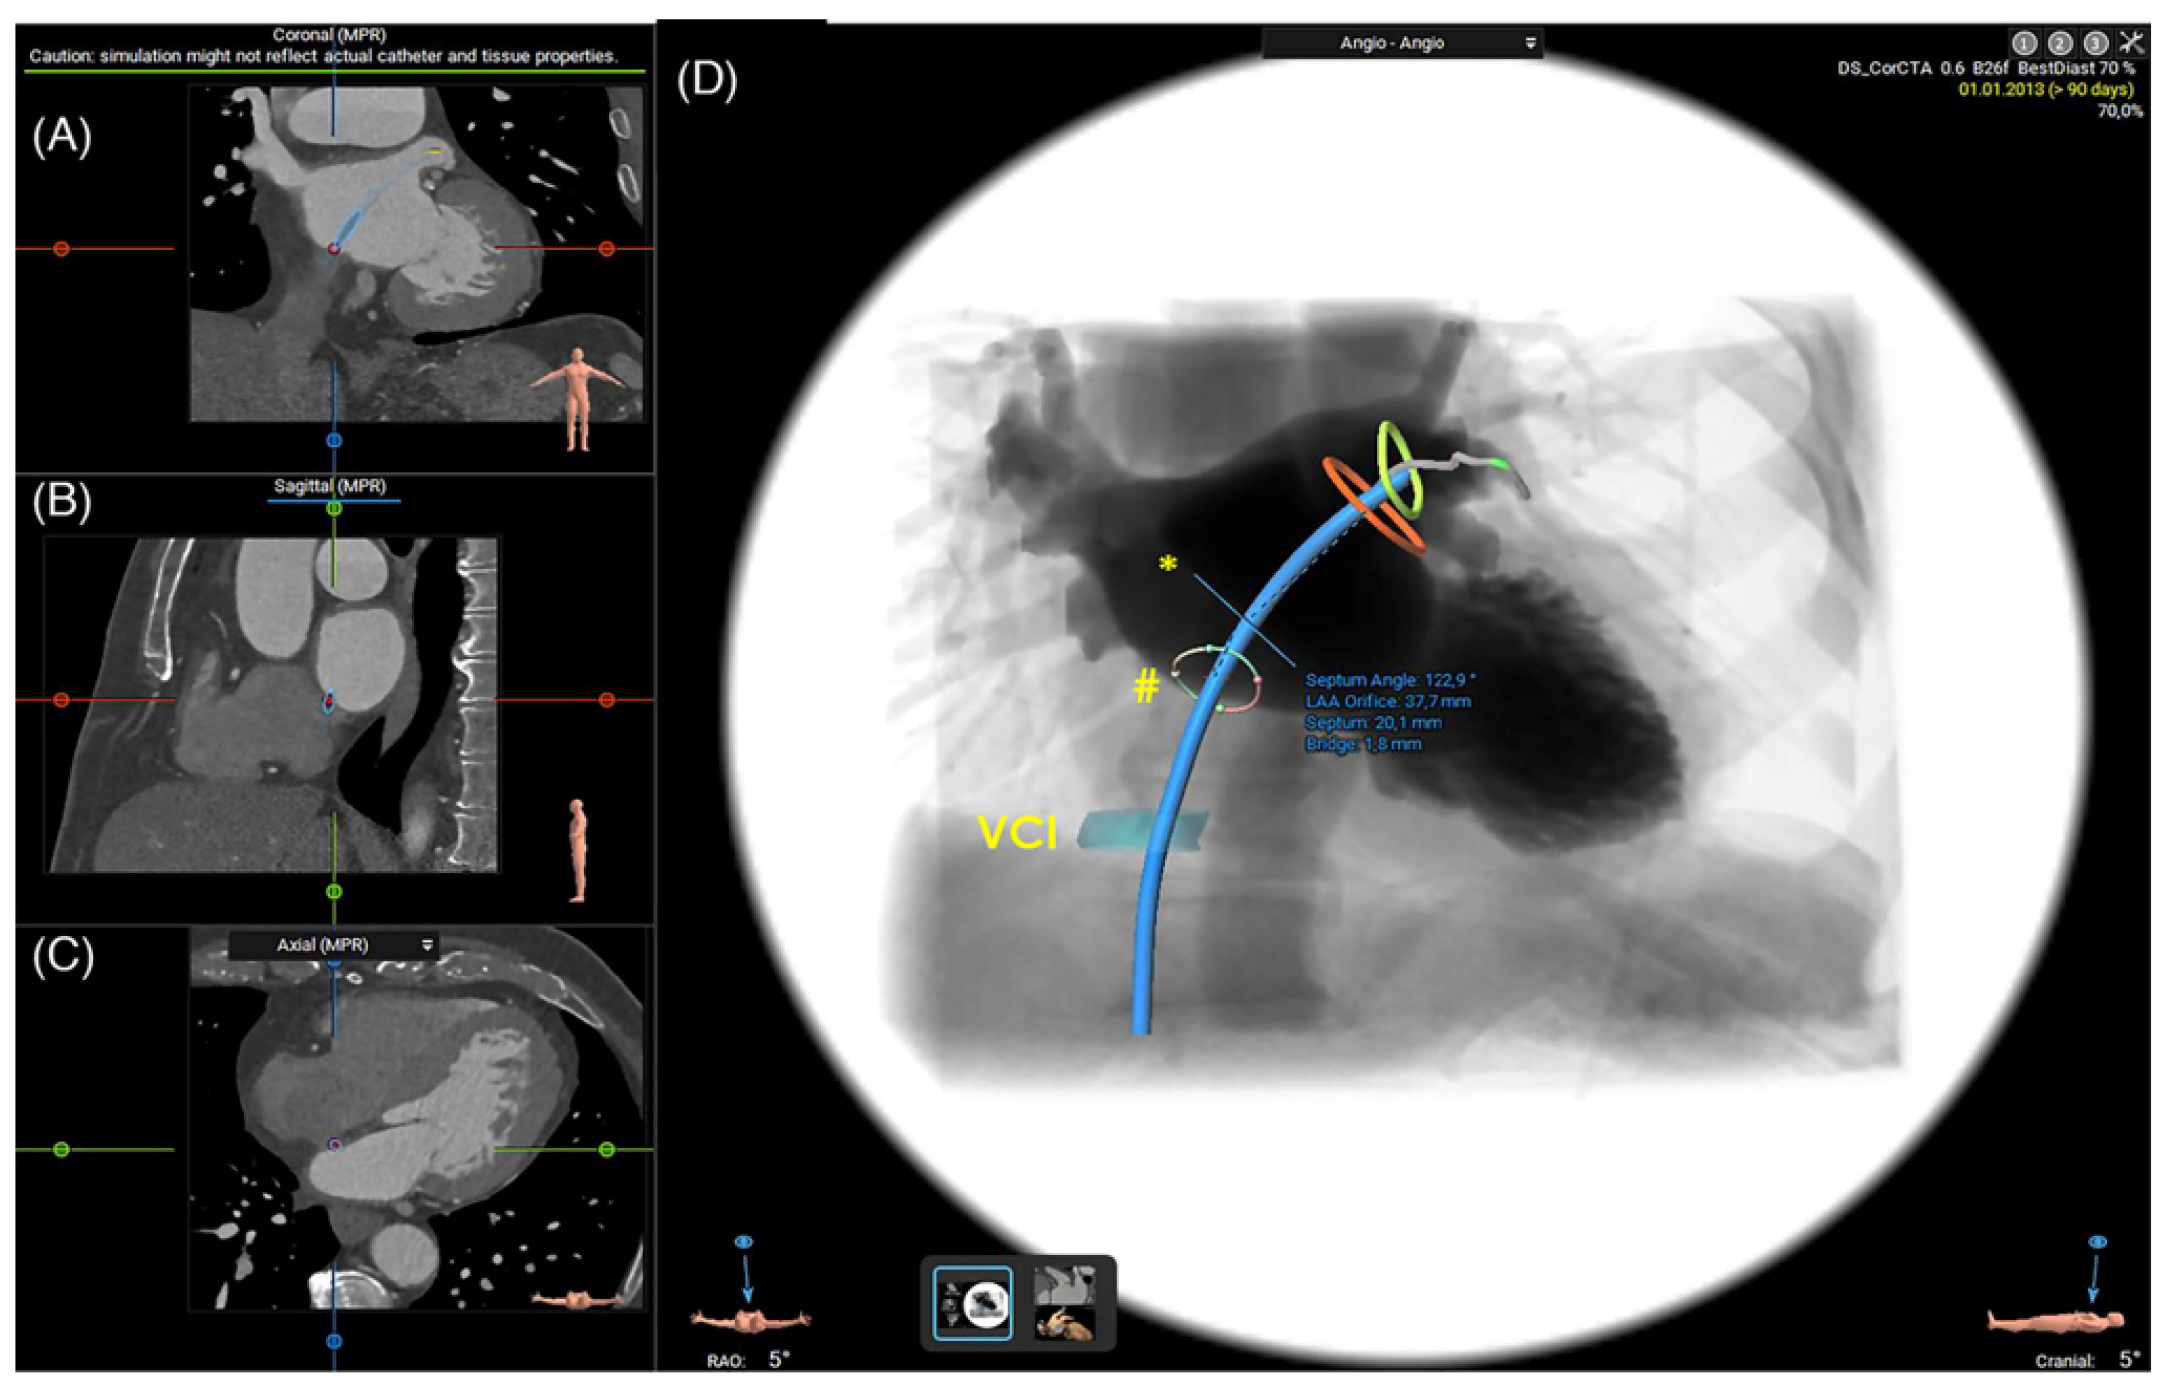

2.1.3. Assessment of the Inter-Atrial Septum

2.1.5. 3D Printing and Virtual Reality

- Hozman, M.; Herman, D.; Zemanek, D.; Fiser, O.; Vrba, D.; Poloczek, M.; Varvarovsky, I.; Obona, P.; Pokorny, T.; Osmancik, P. Transseptal Puncture in Left Atrial Appendage Closure Guided by 3D Printing and Multiplanar CT Reconstruction. Catheter. Cardiovasc. Interv. 2023, 102, 1331–1340. [Google Scholar] [CrossRef]

- Wang, D.D.; Eng, M.; Kupsky, D.; Myers, E.; Forbes, M.; Rahman, M.; Zaidan, M.; Parikh, S.; Wyman, J.; Pantelic, M.; et al. Application of 3-Dimensional Computed Tomographic Image Guidance to WATCHMAN Implantation and Impact on Early Operator Learning Curve: Single-Center Experience. JACC Cardiovasc. Interv. 2016, 9, 2329–2340. [Google Scholar] [CrossRef]